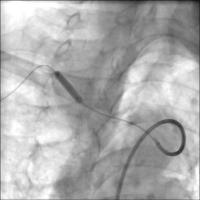

Vordilatation

Abbildung 3: Vordilatation mit Ballon.

Stentposition

Abbildung 4: Freisetzung des selbstexpandierenden Stents (Luminexx 3™, 14x30/135cm, Bard. Technisch war es notwendig, den Draht zurückzuziehen, um eine optimale Stentposition zu erreichen.